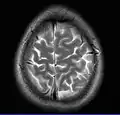

- T2-weighted (T2W) images: CSF is light, but fat (and thus white matter) is darker than with T1. T2-weighted images are useful for visualizing pathology.[26]

Normal axial T2-weighted MR image of the brain